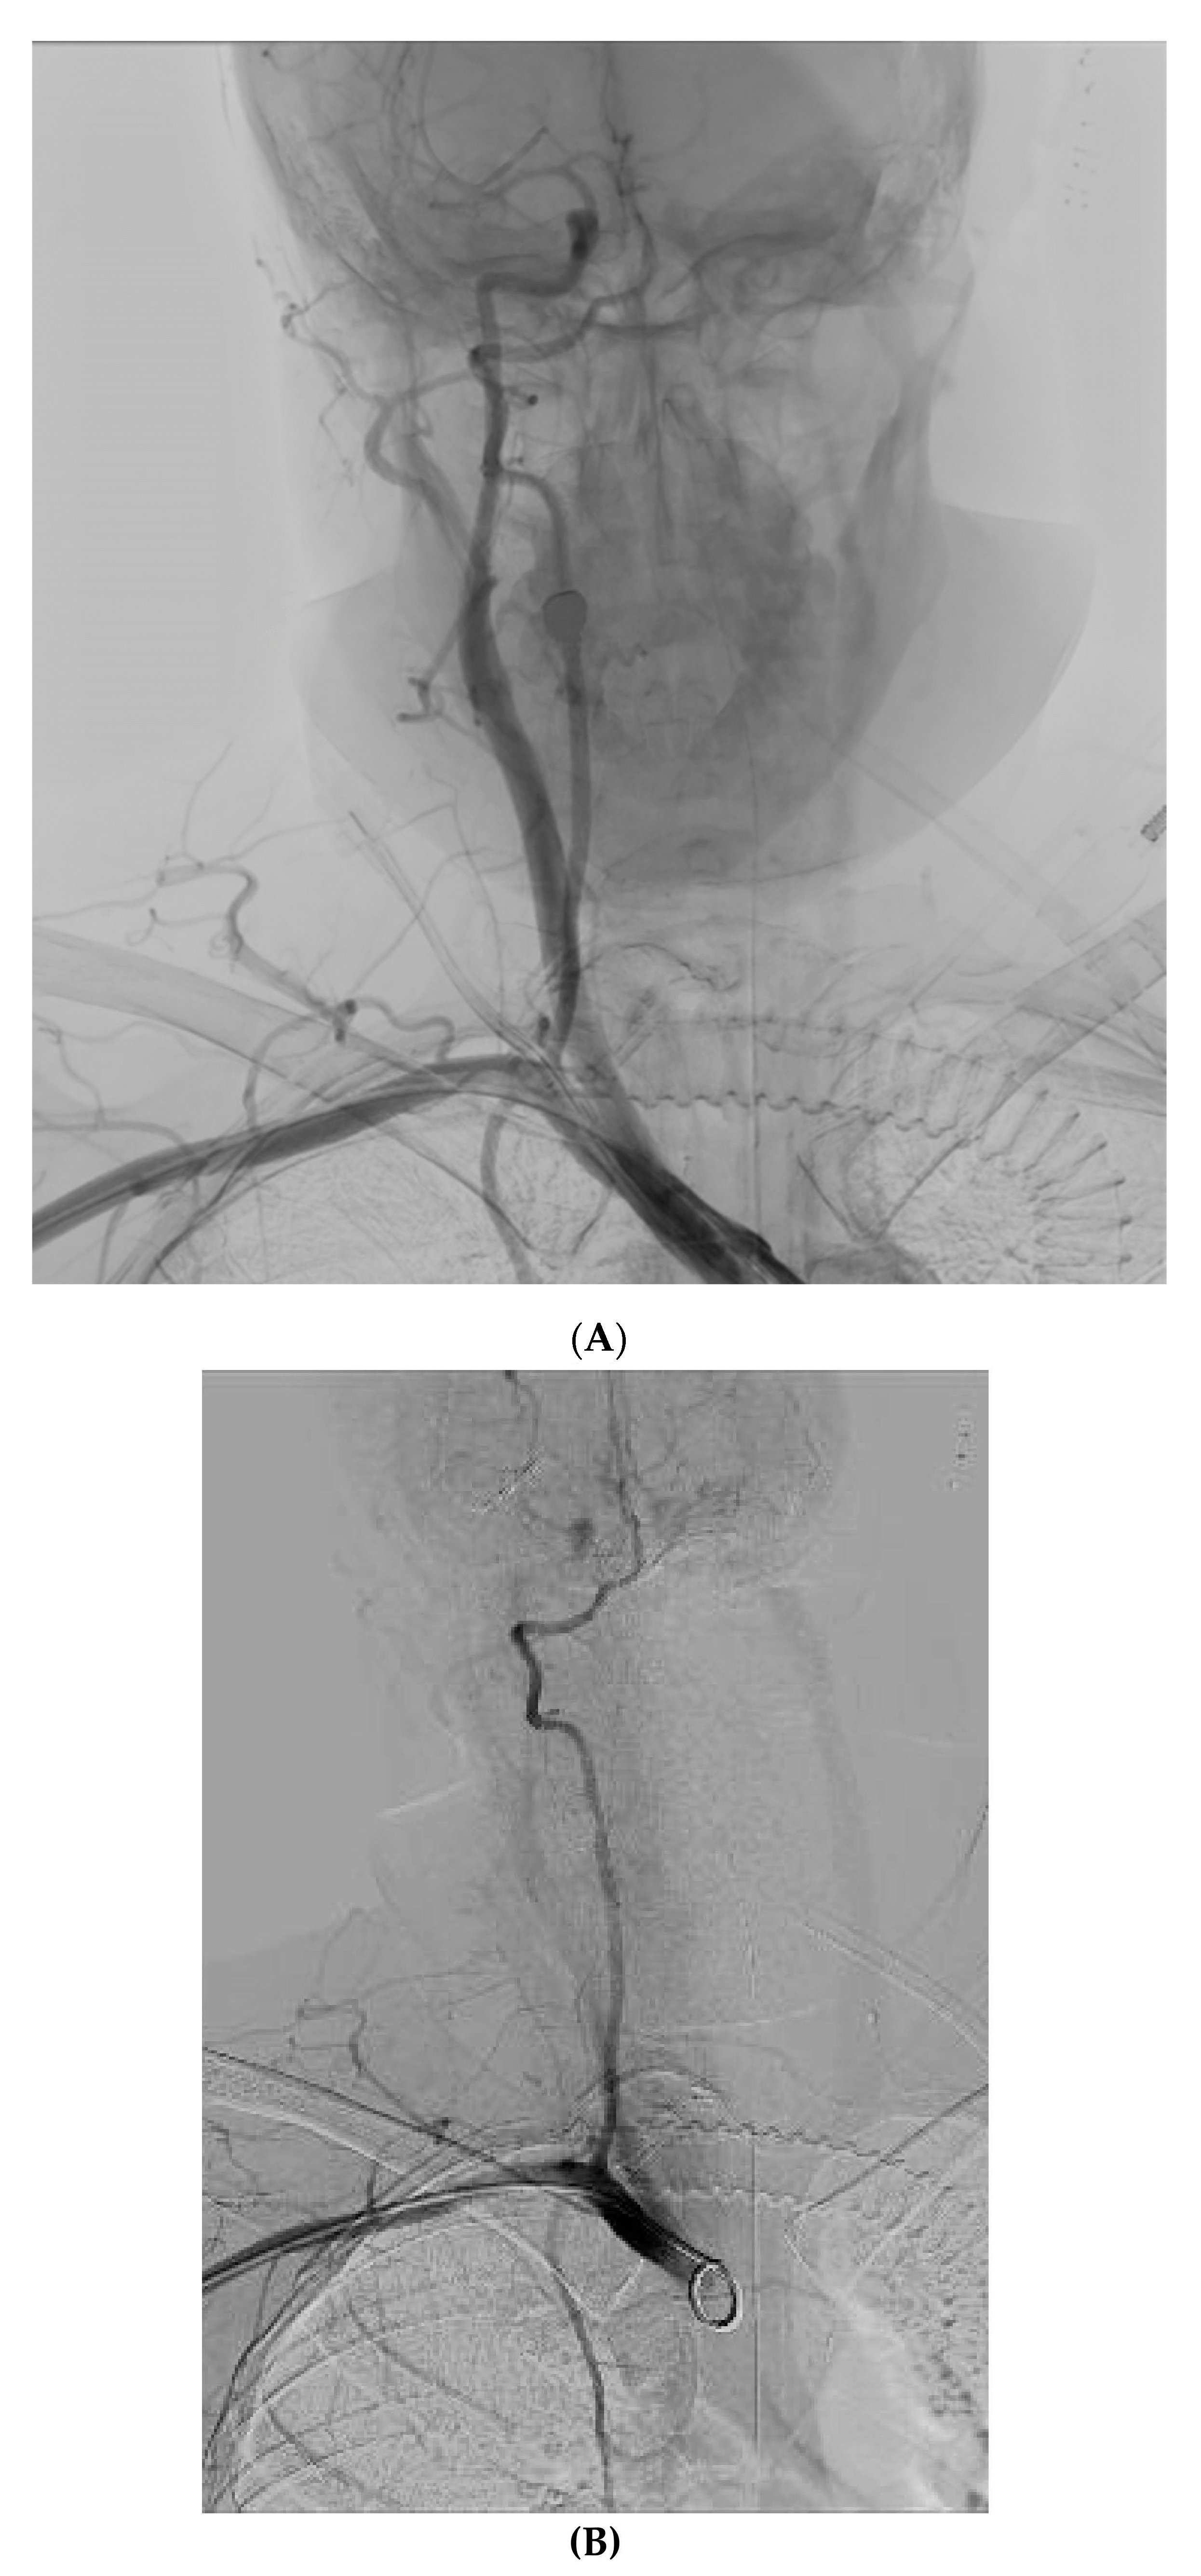

4. Case 3

A 65-year-old male with lung carcinoma was referred for right central venous port removal due to skin ulcer formation and for port placement on the left. After skin antiseptic preparation and local anesthesia, the left subclavian vein (SCV) was accessed using real-time ultrasound guidance in the in-plane approach. The left SCV was entered using aspiration with a saline filled syringe. No pulsatile blood flow was identified. The guide-wire was introduced and followed on fluoroscopy crossing the diaphragm to the right of the spinal column. After the implantable port’s 8F peel-apart sheath was introduced, it was realized that it actually was intra-arterially. The peel-away sheath was removed and a Perclose proglide 6F arterial closure device was introduced and deployed over the guide-wire. After pulling the sutures of the Perclose hemostasis was achieved, unfortunately the sutures inadvertently broke due to excessive pulling (Figure 3A). Manual compression was immediately applied. The left brachial artery was accessed using local anesthesia, under real time US-guidance, with a 5F sheath. A guide-wire was introduced through the 5F sheath and angiography was performed using a diagnostic catheter to identify the site of the extravasation. A 7 × 40 mm Mustang angioplasty balloon was navigated to the extravasation using fluoroscopy and inflated to nominal pressure for 5 min (Figure 3B). After a repeat angiography, a small extravasation was still visible in the left SCA. The balloon was again inflated for 5 min with concomitant manual compression and at the final run, no extravasation was visible (Figure 3C). A few days later, the right port was removed and a right PICC was inserted for vascular access.

Figure 3. (A) Contrast extravasation from the left SCA, after closure device failure. (B) Manual compression with balloon assisted inflation at the site of the extravasation. (C) Final result, with no extravasation.